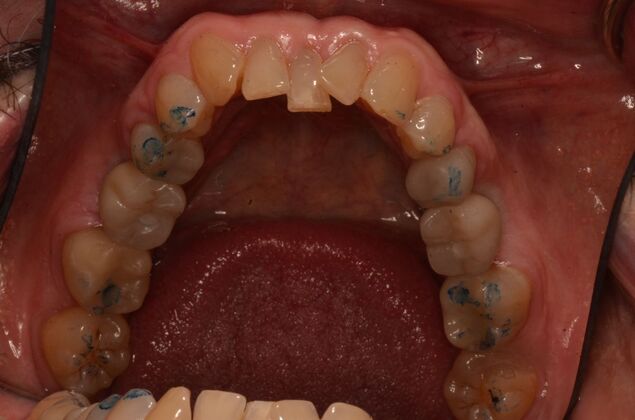

Patient lost lower first molars and required two lower implants with two lower screw retained crowns